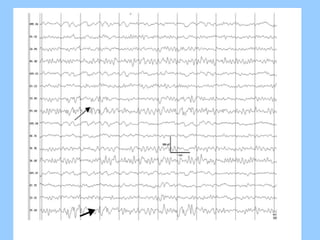

1. The document discusses EEG patterns and findings in various neurological conditions seen in children. It includes descriptions of normal EEG findings as well as abnormal patterns seen in conditions like absence seizures, West syndrome, benign childhood epilepsy with centrotemporal spikes, Lennox-Gastaut syndrome, non-convulsive status epilepticus, subacute sclerosing panencephalitis, and herpes encephalitis.

2. Case studies are presented with clinical histories and EEG findings to illustrate different pathologies. Treatment options are also mentioned for many of the conditions.

3. International standards for EEG electrode placement and recording parameters are reviewed. Characteristics of different EEG waves, amplitudes, and patterns are described.